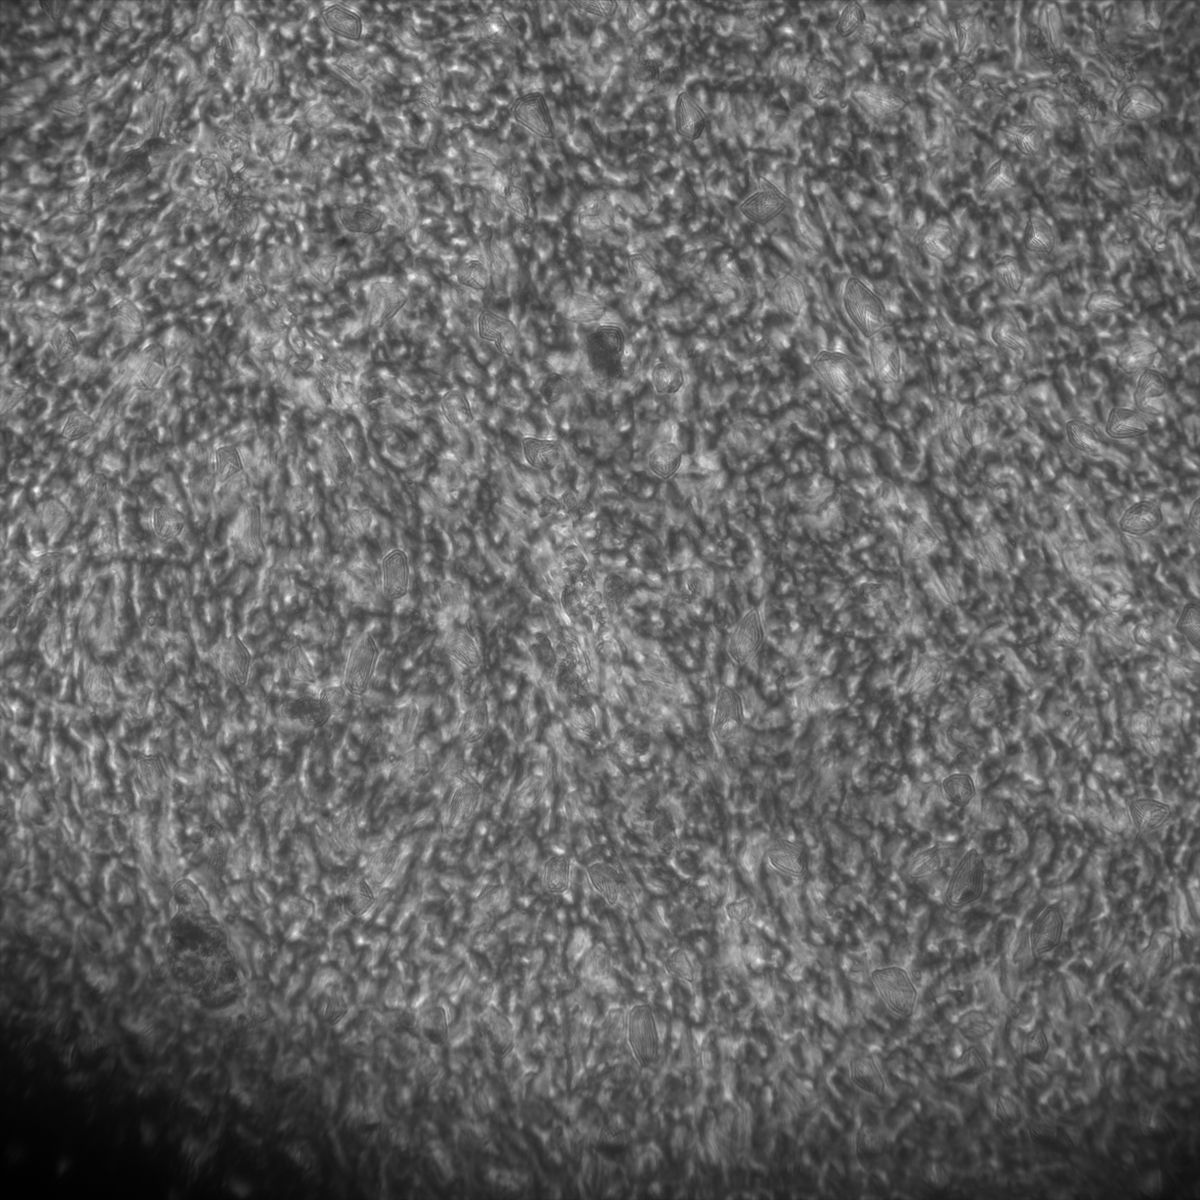

Tubulin

Overview 2

Tubulin - Bip

Tubulin - Nuc

Actin